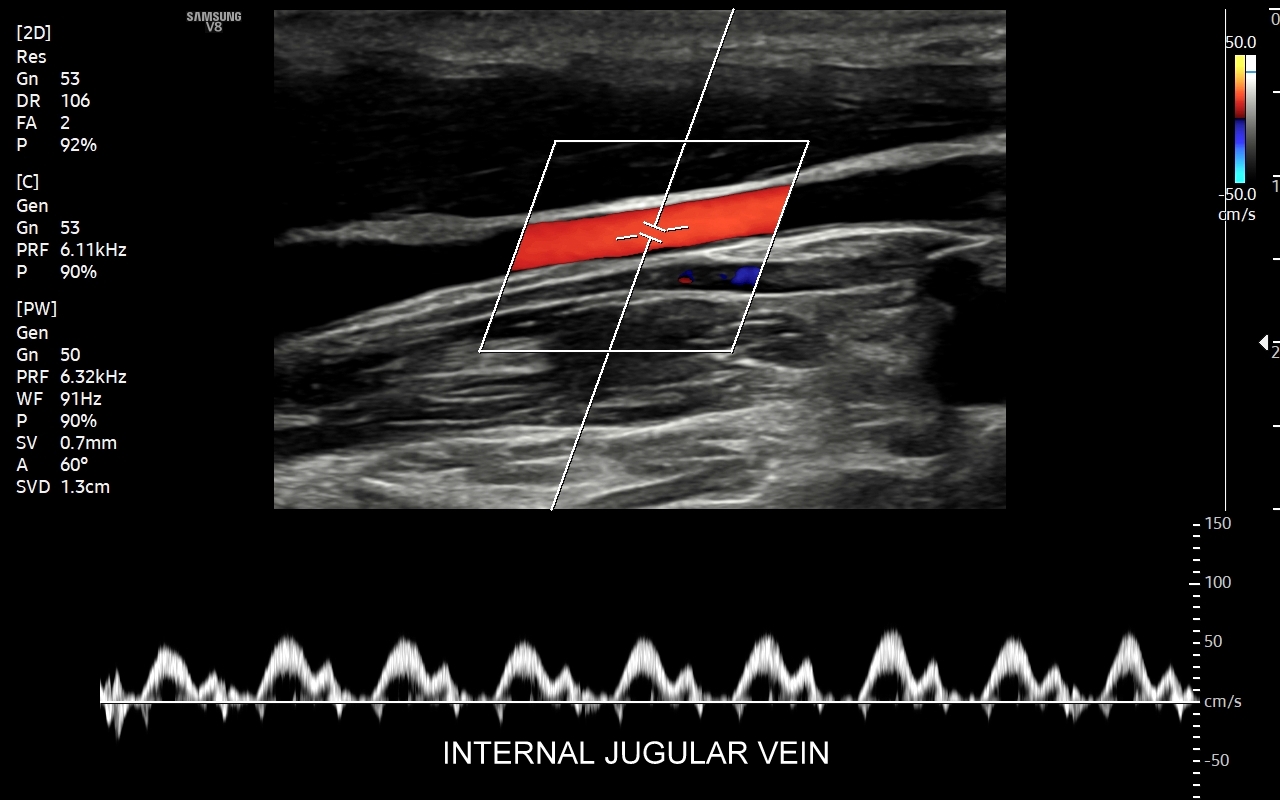

USG Doppler żył szyjnych i kończyn górnych

Badanie USG Doppler żył szyjnych, podobojczykowych i żył kończyn górnych najczęściej wykonywane jest z powodu spontanicznych zakrzepów pojawiających się w przebiegu takich schorzeń jak odwodnienie, nadużycie napojów „energetycznych”, zespoły uciskowe, zespół górnego otworu klatki piersiowej, choroby nowotworowe i mieloproliferacyjne, trombofilia, czy jatrogenne powikłania cewnikowania żył. U osób zdrowych, tj. bez obciążeń trombofilnych, zakrzepica w zakresie żył obręczy kończyny górnej zwykle występuje jako powikłanie ucisku, np. przez mięśnie u osób podnoszących ciężary na siłowni albo przez ramiączka ciężkiego plecaka podczas wędrówek krajoznawczych. Objawami zakrzepicy żyły ramiennej, pachowej, podobojczykowej, czy żylnego pnia ramienno-głowowego zwykle są uczucie dyskomfortu w kończynie górnej, ból, ograniczenie ruchomości, zasinienie i obrzęk kończyny górnej, pojawienie się poszerzonych naczynek na ścianie klatki piersiowej.

Czym jest zakrzepica żył? Zakrzepica żylna polega na powstaniu skrzepu wewnątrz naczynia żylnego i wtórnym rozwoju stanu zapalnego w okolicy naczynia. Choroba dotyczyć może układu powierzchownego żył lub żylaków, a w tym wypadku nie jest zwykle stanem niebezpiecznym; a także układu głębokiego żył, co z kolei jest stanem potencjalnie zagrażającym życiu, gdyż może sprowokować zatorowość płucną. Zakrzepica żył głębokich (ang. deep venous thrombosis DVT) częściej występuje w obrębie żył kończyn dolnych, następnie w obrębie żył biodrowych, rzadziej w żyle podobojczykowej i żyłach głębokich kończyny górnej. Przyczyny zakrzepicy żylnej są różnorodne i obejmują m. in. długie podróże, długotrwałe unieruchomienie, operacje ortopedyczne, chirurgiczne i szczękowe, urazy tkanek miękkich oraz złamania kości, genetycznie uwarunkowane trombofilie, nowotwory złośliwe, odwodnienie, infekcje miejscowe i ogólnoustrojowe. W przypadku zakrzepicy żyły podobojczykowej klasyczną jej przyczyną jest ucisk; w swojej praktyce klinicznej dr Szczepański spotkał się z zakrzepicą podobojczykową wywołaną m. in. przez ciężki plecak, wyciskanie sztangi na siłowni, czy przez uprawianie wspinaczki skałkowej. W warunkach szpitalnych zakrzepica żyły podobojczykowej lub żyły szyjnej wewnętrznej może pojawić się w wyniku zakładania cewników dożylnych. Sprawne wykrycie zakrzepicy w badaniu USG, a następnie wdrożenie odpowiedniej terapii uchronić może pacjenta przed powikłaniami ostrymi (np. zator płucny), jak i opóźnionymi (np. zespół pozakrzepowy).